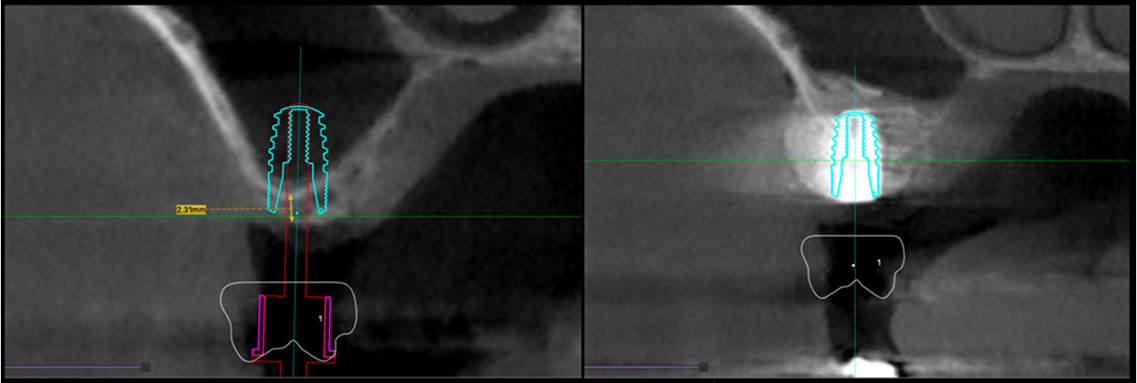

Implant placement should be dictated by the ideal future tooth position. Following tooth loss, there is always inevitable loss of surrounding bone and gum. As a result, to provide optimal conditions for placement of dental implants, bone and gum grafting may be required.

Similarly, for upper molar implants, some cases may require raising the sinus floor to provide adequate space for the implants to be surrounded by bone.

At North Shore Prosthodontics, we are able to provide all these services, from treatment planning using the most up to date Cone Beam CT scans to grafting, implant surgeries and insertion of provisional and definitive crown / bridge in one location by Dr Lim.

Image above depicting implant planning with 3D imaging. The left image shows where the implant should be according to the correct crown position. The implant can be seen located into the sinus, thus a sinus lift and bone graft were performed with a simultaneous implant placement in the desired position.

This was completed in one appointment.